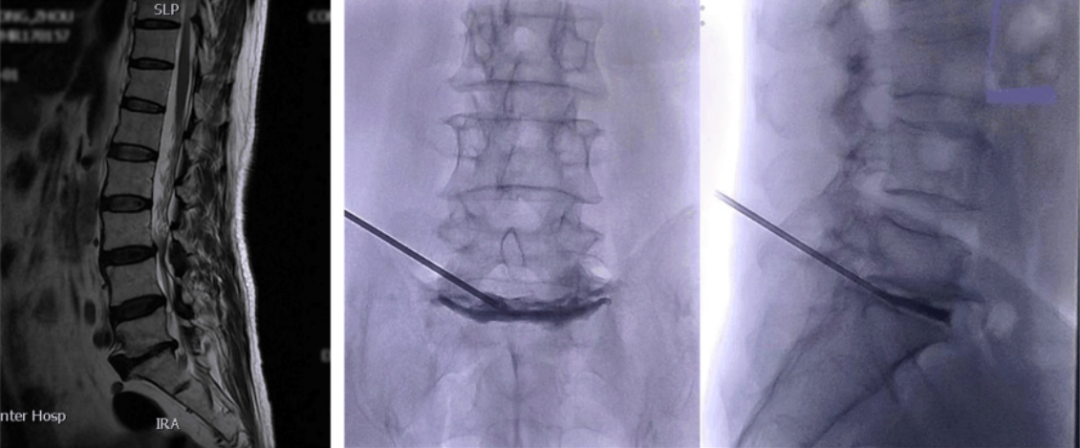

图: 典型的手风琴现象左图为站立位X线片,右图为仰卧位CT。站立位负重时的椎间盘与仰卧位(不负重)椎间盘塌陷程度不同,且侧凸角度也不同(分别为25°和14°)

图: 术前影响资料可见退行性侧凸伴多节段椎间盘真空征

图: 与典型病例相似的另一退变性侧凸患者,术前存在手风琴现象,经多节段PCD术后冠状位得到10°的纠正且恢复部分腰椎前凸